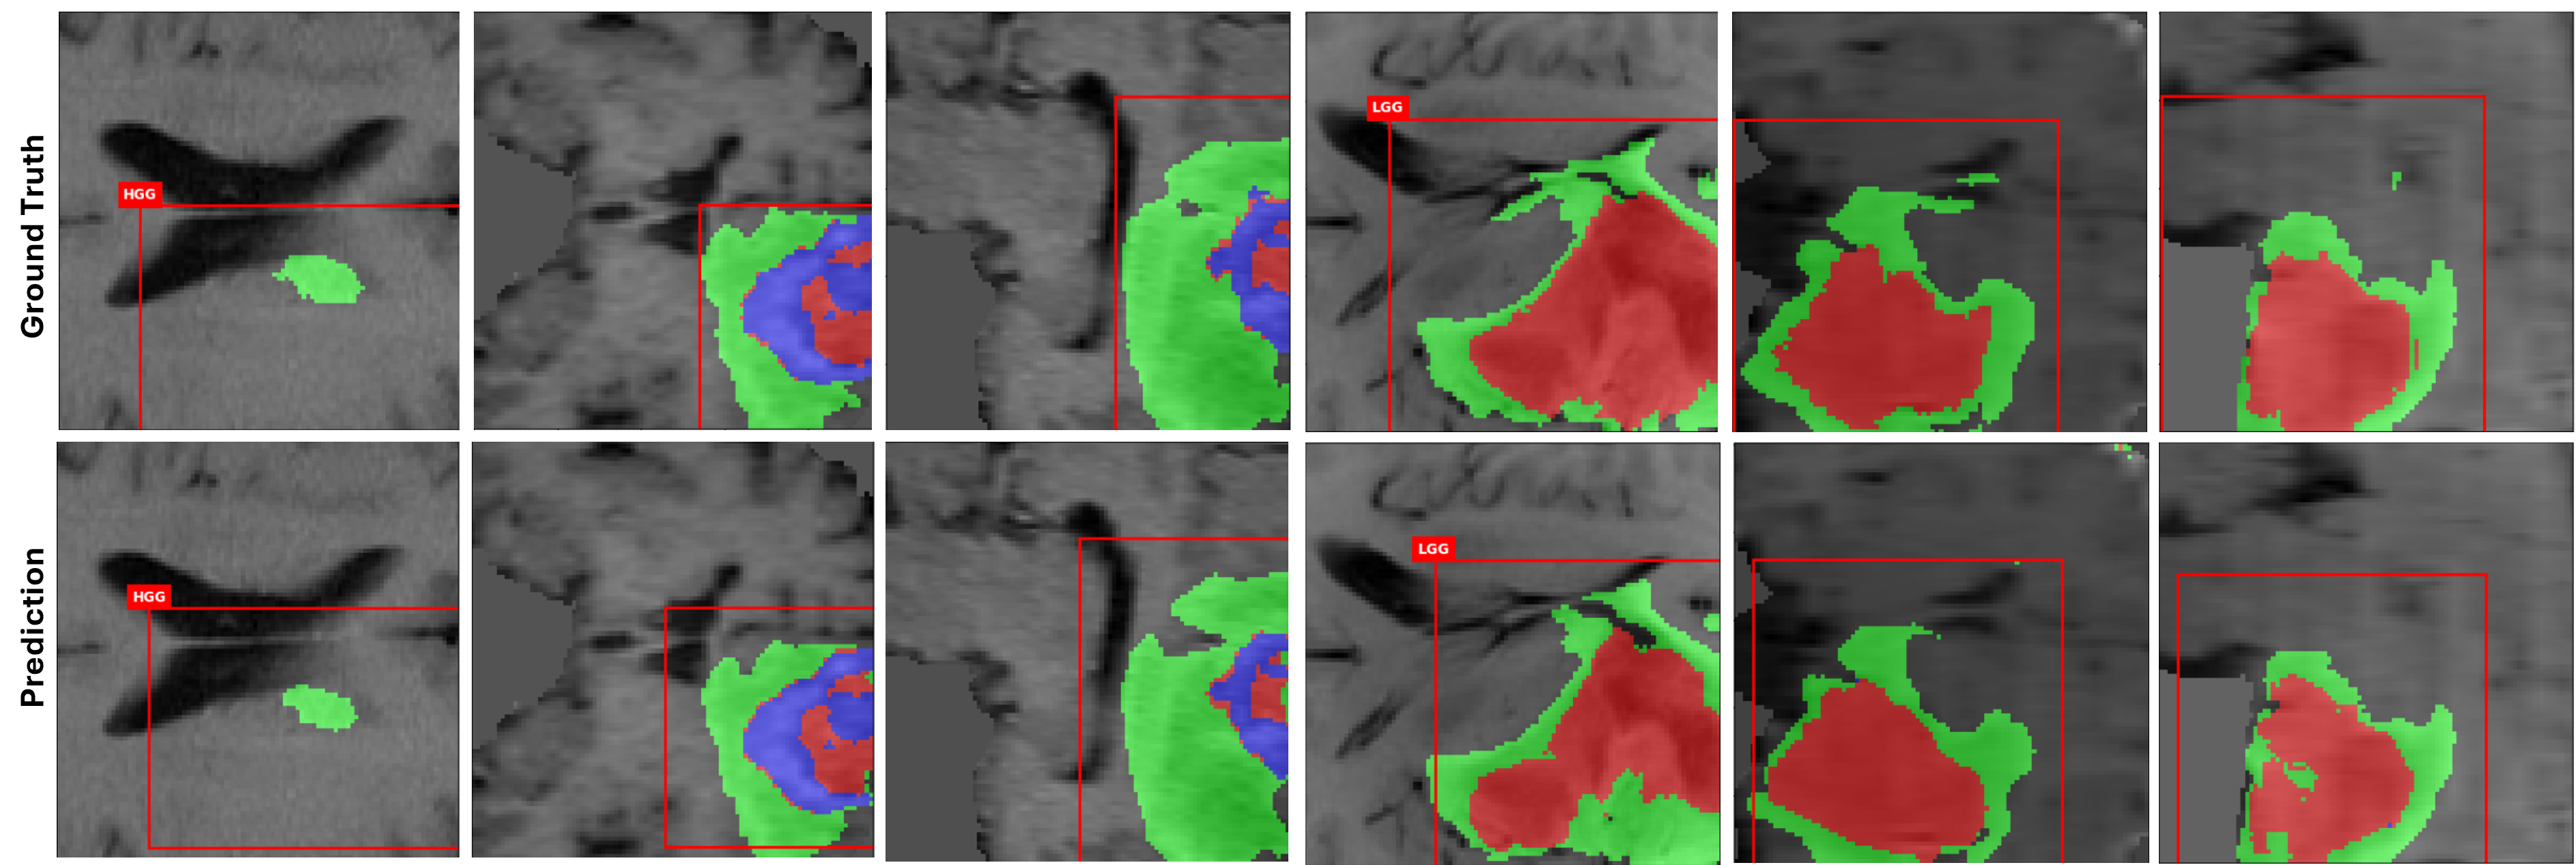

Figure 4: Qualitative results for MTMed3D: The top row represents the Ground Truth, while the bottom row shows the outputs of MTMed3D. The left three columns depict HGG samples, representing three brain directions, and the right three columns show LGG samples. Red indicates the Tumor Core, green represents the Whole Tumor, and blue denotes the Enhanced Tumor.

Table I reports the best and average results over five-fold cross-validation on BraTS 2018 and 2019 for detection, segmentation, and classification, where the best fold is defined as the one with the highest average performance across all three tasks. mAP@0.1:0.5 refers to the mAP computed over IoU thresholds from 0.1 to 0.5 with a step size of 0.05, while mAP@0.5 denotes the result at a fixed IoU of 0.5. Since the BraTS dataset was originally designed for segmentation and classification tasks, there are limited existing 3D detection methods evaluated on this dataset. To establish a fair comparison, we implemented a 3D RetinaNet with a ResNet-FPN backbone and trained it using the fold that achieved the best performance in our cross-validation experiments. This model served as our detection baseline. We also compared our proposed model against nnDetection and MedYOLO [sobek2024medyolo], though their reported results are available at mAP@0.5, a dash (“-”) indicates that no relevant data were available. Table II presents the detailed results, showing that MTMed3D outperforms these methods, possibly due to the hierarchical Transformer encoder’s ability to effectively capture spatial context. The strong mAP and mAR values demonstrate the effectiveness of our model in accurately localizing brain tumors in 3D medical images. While our model outperforms existing methods on BraTS, further validation on additional datasets is necessary to assess its generalization capability in broader detection scenarios. In Figure 4, the red rectangular boxes represent the predicted detection bounding boxes.

In Table I, the model shows strong segmentation performance with high Dice and low HD across all tumor regions. Table III compares the segmentation performance of our model with several state-of-the-art (SOTA) methods leading in the BraTS 2018 challenge rankings. Since BraTS requires server submission for test evaluation and lacks detection labels, we report five-fold cross-validation results to ensure consistency across the three tasks. MTMed3D achieves the highest Dice scores. Although our model slightly lags behind some methods in HD for specific components, the overall performance of MTMed3D remains competitive. Figure 4 presents the output results of our multi-task model. Comparing the ground truth with the segmentation results, while there are little differences in some areas, such as the boundary of the WT and TC, the overall results are closely aligned with the ground truth.

Table I details MTMed3D’s classification performance on the BraTS 2018 and 2019 datasets. Our average 5-fold cross-validation results show higher sensitivity but lower specificity, suggesting a bias toward the majority HGG class. We applied Focal Loss to address this class imbalance, but it did not lead to improved performance. Table IV compares the classification performance of our model with SOTA methods on the BraTS 2018 dataset. According to Table IV, other methods outperform ours. This is primarily because these methods operate on 2D slices rather than directly on 3D volumes and rely on dedicated preprocessing designed for classification. For instance, Mask R-CNN[zhuge2020automated], CNN [hafeez2023cnn], and SE-ResNeXt [linqi2022glioma] are all based on 2D inputs. However, our model is a multi-task model that processes all tasks on the same 3D data, without separate 2D preprocessing or classification steps. In addition, ConvNet [zhuge2020automated] uses a two-stage pipeline that segments the tumor and then applies additional data augmentation to the segmented regions before training a classification model. MTMed3D is an end-to-end model, eliminating the need for manually designed intermediate steps and simplifying the overall training and inference pipeline. Moreover, SE-ResNeXt applies transfer learning to enhance generalization. In contrast, our multi-task model not only ensures the performance of each task but also maintains a balance across tasks, preventing any single task from dominating training. This constraint limits the use of task-specific optimization or pre-trained weights that could disproportionately favor one task over others. Figure 4 shows classification results above the red bounding boxes, with both HGG and LGG correctly classified.